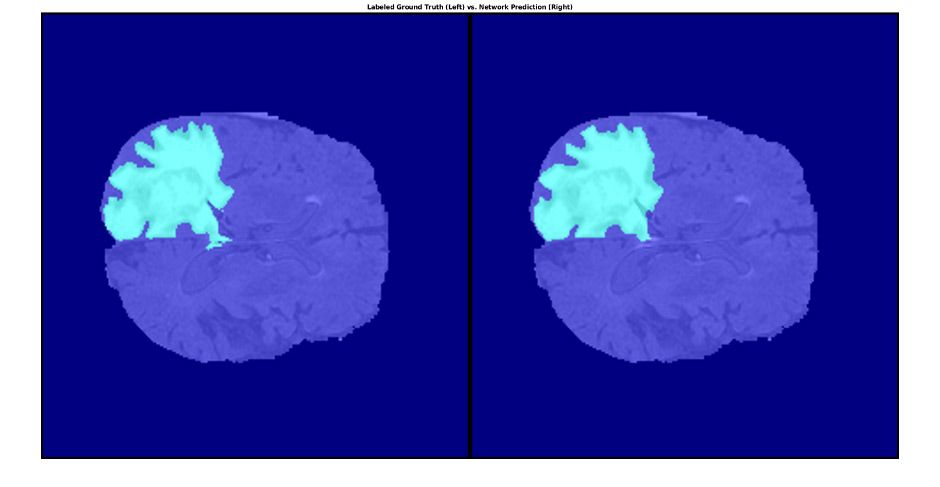

Brain MRI showing tumor tissue segmented using medical image processing.

Segmented tumor in brain tissue using MATLAB with labeled ground truth (left) and network prediction (right). (See code.)